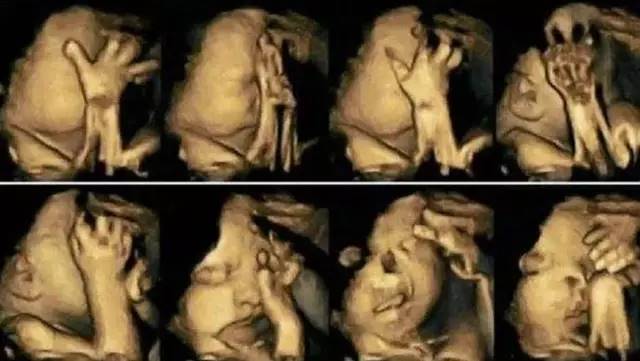

後來,通過超音波檢查,女子發現寶寶似乎個性非常活潑,在肚子裡不停翻身,一下子摸嘴巴,一下子又抓抓耳朵,甚至會摀著臉就像在哭泣一樣,逗得她開心直呼:「孩子會做鬼臉呢!將來一定很聰明!」